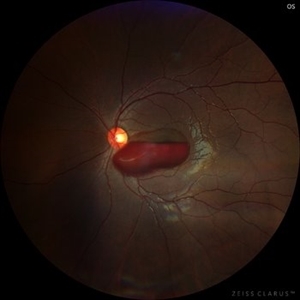

Ruptured Macroaneurysm

Fundus photograph of an 45-year-old woman with a ruptured macroaneurysm. 1st day of presentation.

Photographer: Karen Flores Guevara

Condition/keywords: ruptured macroaneurysm